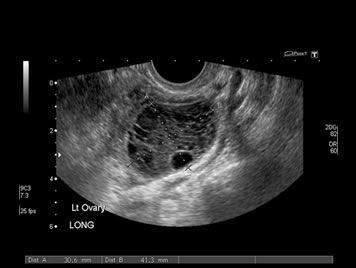

Gynecological Ultrasound

A Gynecological scan involves ultrasound assessment of the uterus, ovaries and the parts of the pelvis which are nearby to diagnose conditions such as uterine fibroids, adenomyosis, endometrial polyps and ovarian cysts.